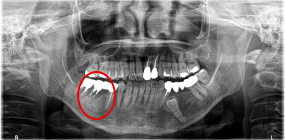

右下奥の歯が、グラグラして噛むと痛い。

治療内容

歯根の周りの骨が全く無い状態でしたので、保存することができず抜歯しました。3本歯がないところに2本インプラントを埋入しました。

Before

※赤丸を抜歯しました。

After